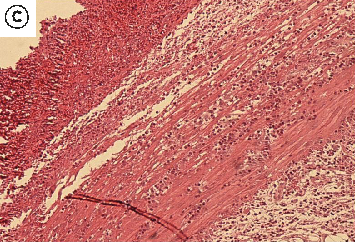

Figure 6

The Healing Effect of Aloe Vera Gel on Acetic Acid-Induced Ulcerative Colitis …